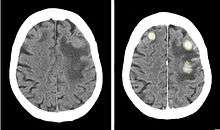

Iodinated contrast is a form of intravenous radiocontrast (radiographic dye) containing iodine, which enhances the visibility of vascular structures and organs during radiographic procedures. Some pathologies, such as cancer, have particularly improved visibility with iodinated contrast.

Iodinated medium may also be either ionic or non-ionic. The ionic type tends to create a high osmolality in blood and may cause a contrast media reaction in some individuals, which may be life-threatening for those with certain medical conditions. The non-ionic form decreases this risk, but is much more expensive. The non-ionic contrast media is much more widely used today.